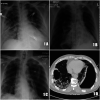

COVID-19 is a pandemic caused by SARS-CoV-2, primarily affecting the respiratory tract. Pulmonary complications of COVID-19 may include acute respiratory distress syndrome and pulmonary embolism. Pneumothorax has been recently reported in association with COVID-19. We report a case of COVID-19 pneumonia with bilateral spontaneous pneumothorax with no known underlying lung disease or risk factors.